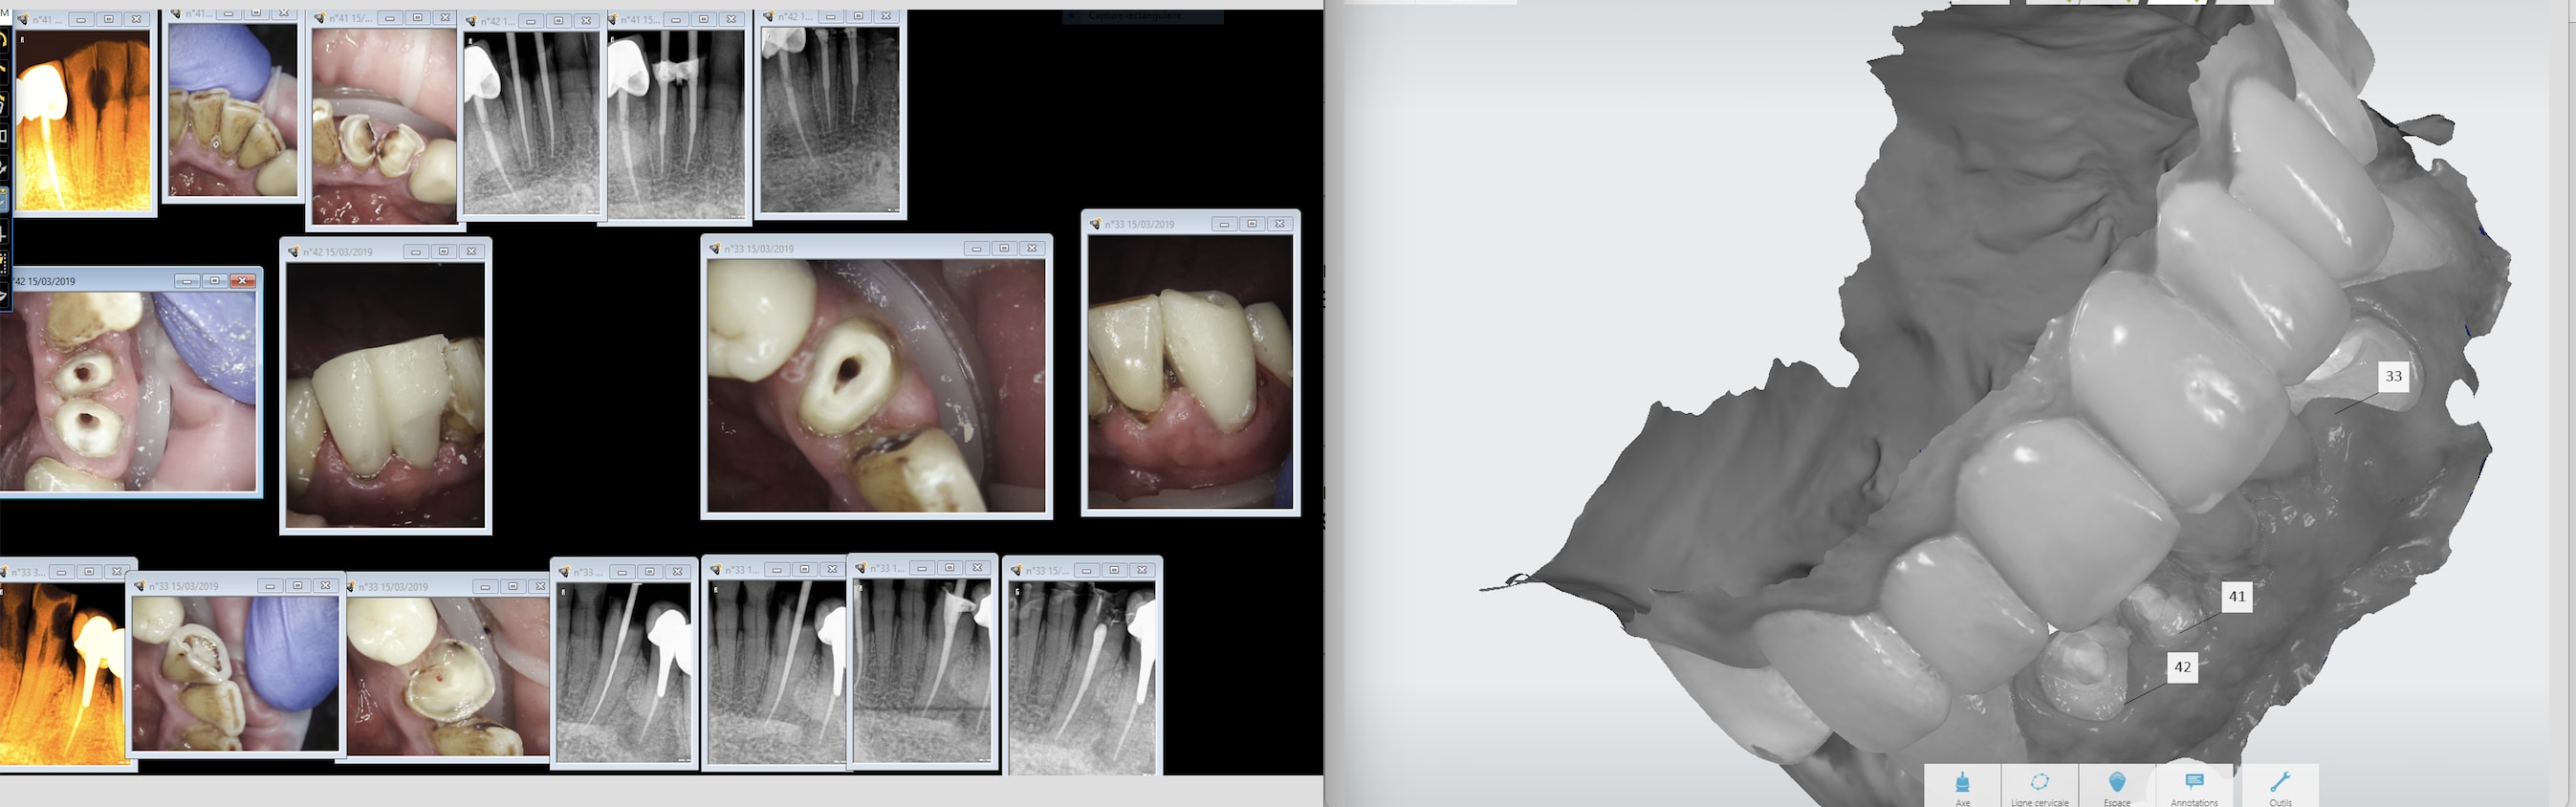

C'est taillé pour tout type d'exercice. Trios a même pensé à adapter sa technologie au meilleur système de santé au monde : scan post pour les inlay cores. Les endos sont offertes, faut pas se priver. -)))

Capture d écran 2019 03 15 22.16 - Eugenol

Capture d écran 2019 03 15 22.17 - Eugenol

Img 20190316 101214 bijasu - Eugenol

Img 20190316 102709 qbtvtg - Eugenol